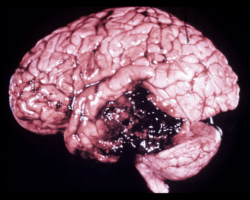

Week 13: Gut & Brain Health Part 2

The metabolic model of preventing and reversing cognitive decline.